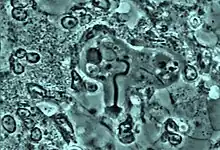

Début de phagocytose du noyau d'un globule blanc par l'amibe Entamoeba gingivalis dans un cas de parodontite chronique